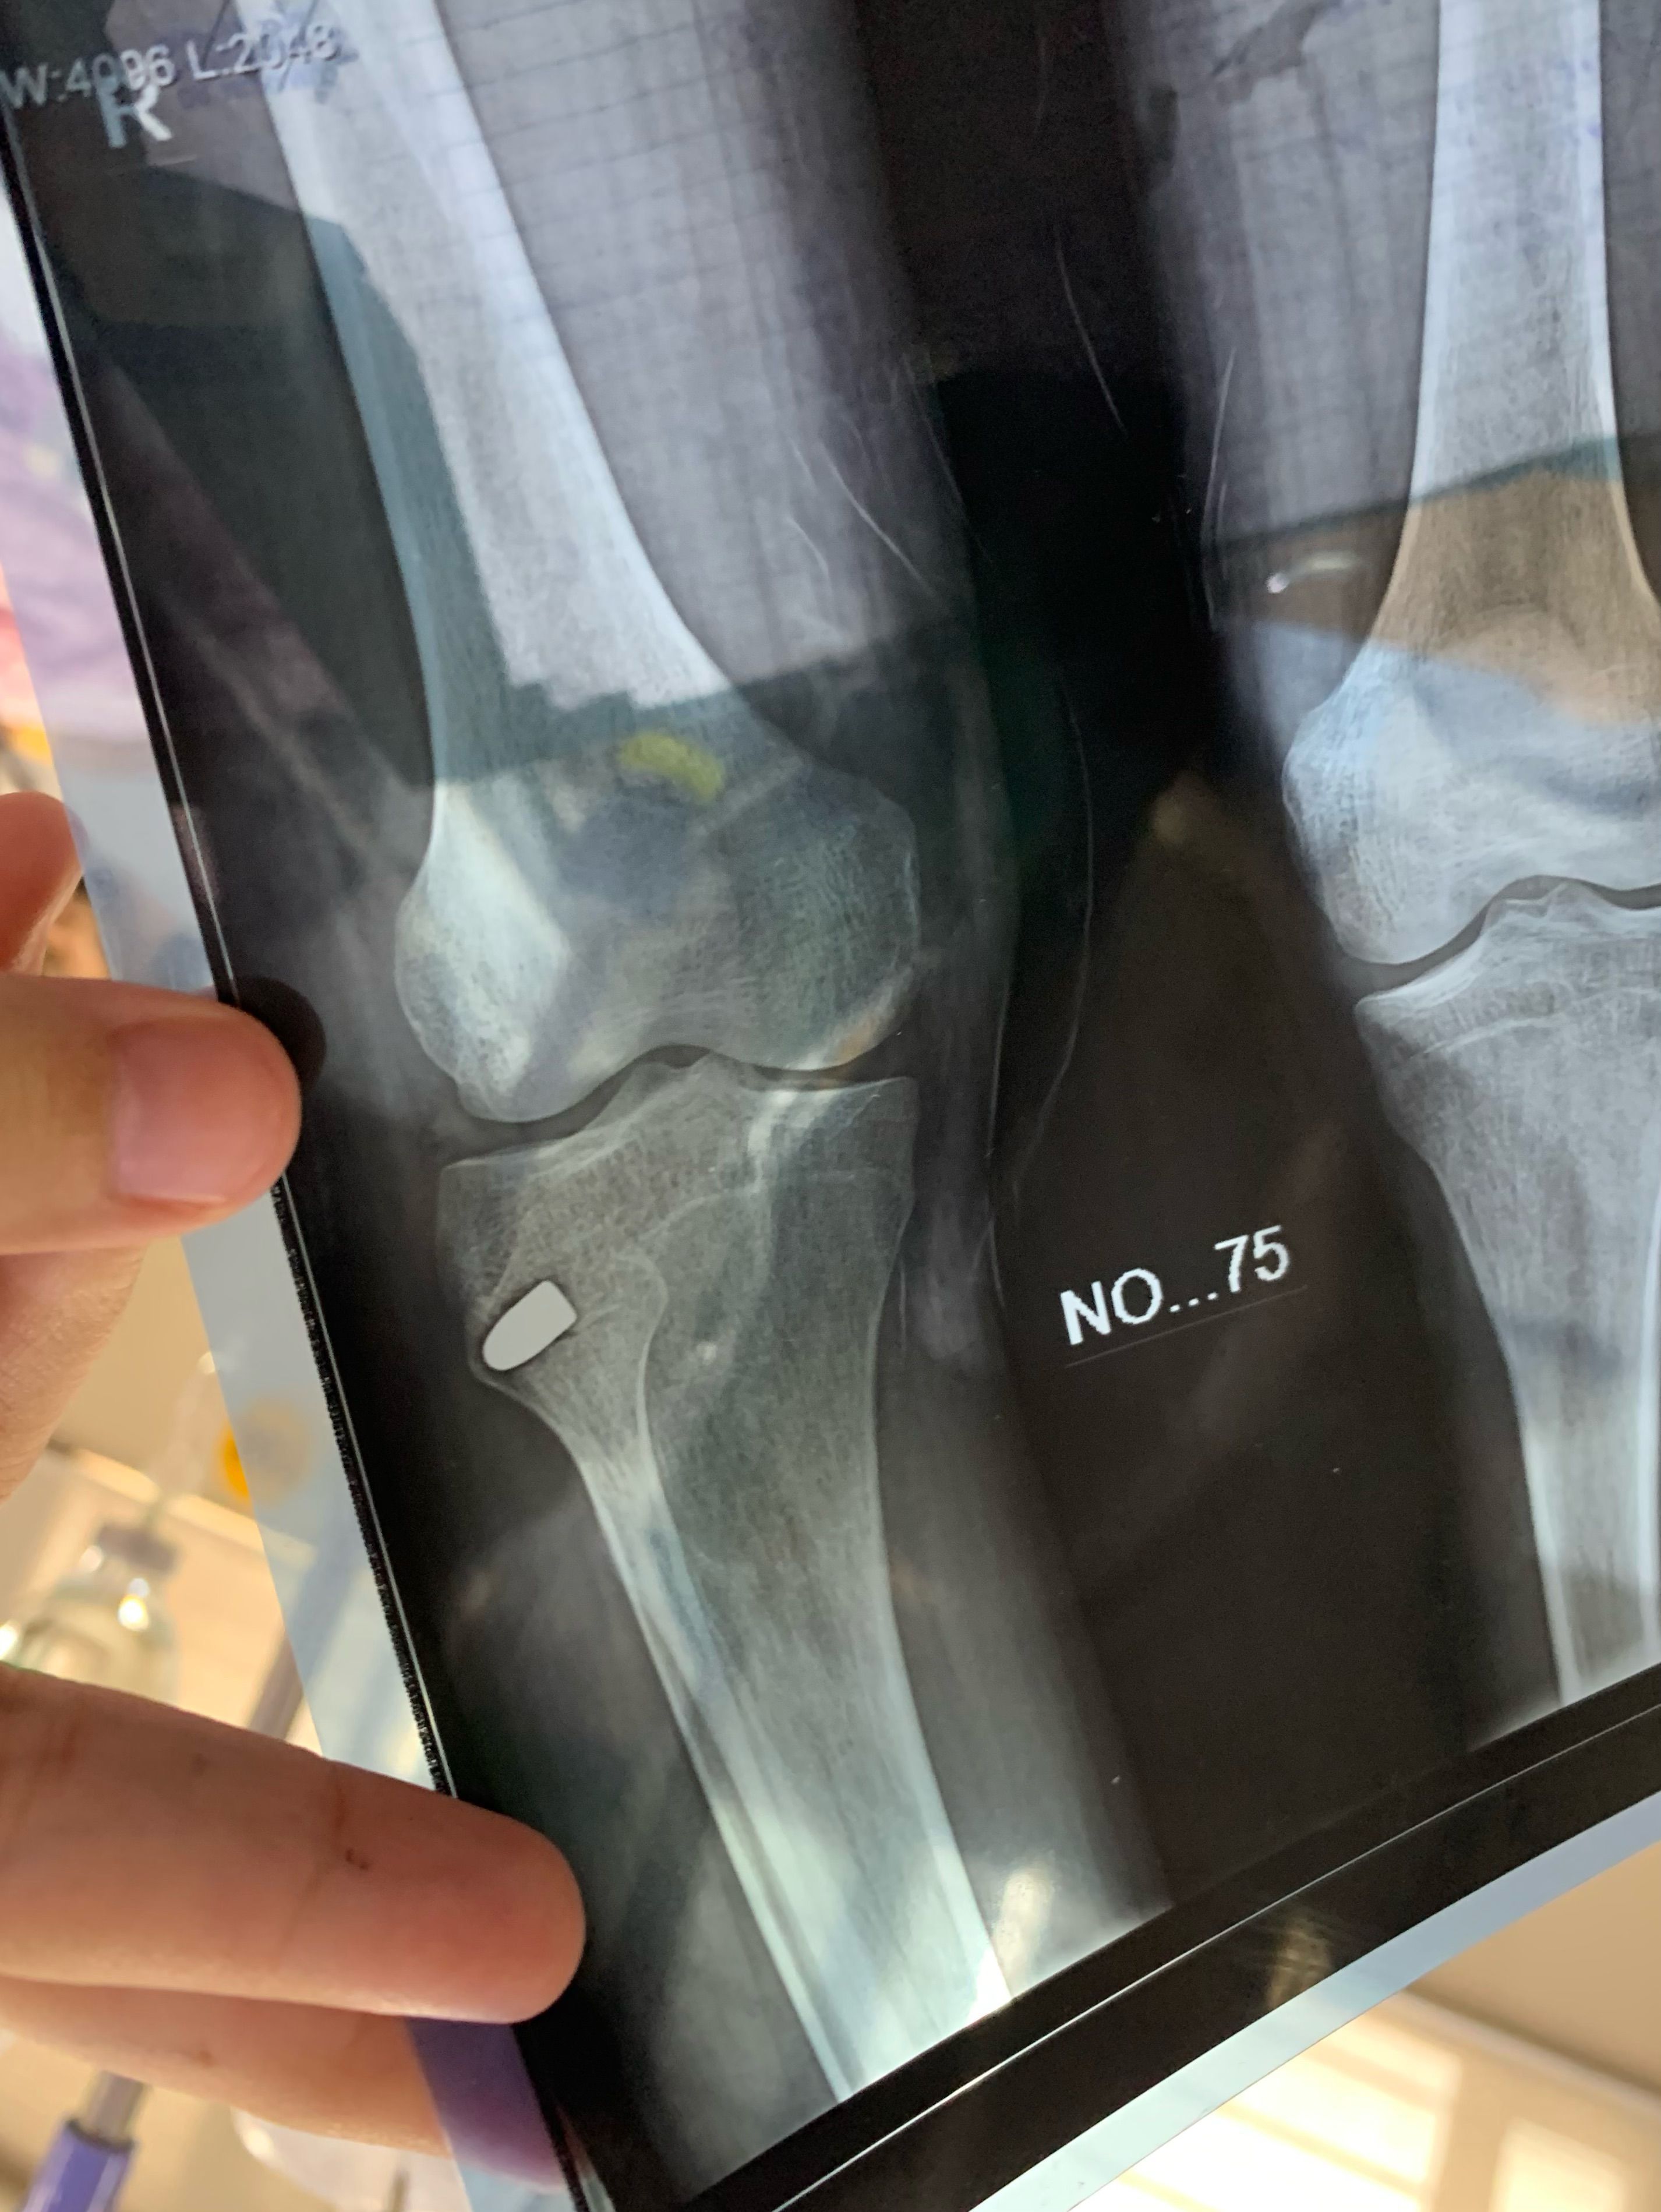

Case: A 35 year old man came to ER and was shot multiple times by a pistol. -2 shots in the abdomen -1 near the heart -2 in the lower limbs. One of the bullet was left in the limb as it wasn’t causing any difficulty in mobility. New researches say that if a vessel is not being occluded and the bullet is not causing damage to tissues it’s better to leave it there. Because if the bullet is removed it can cause large scar and can even lead to excessive bleeding. He was admitted for several days as one bullet causes Liver Cirrohsis, the patient showed good prognosis and upon complete recovery and was discharged from the hospital.